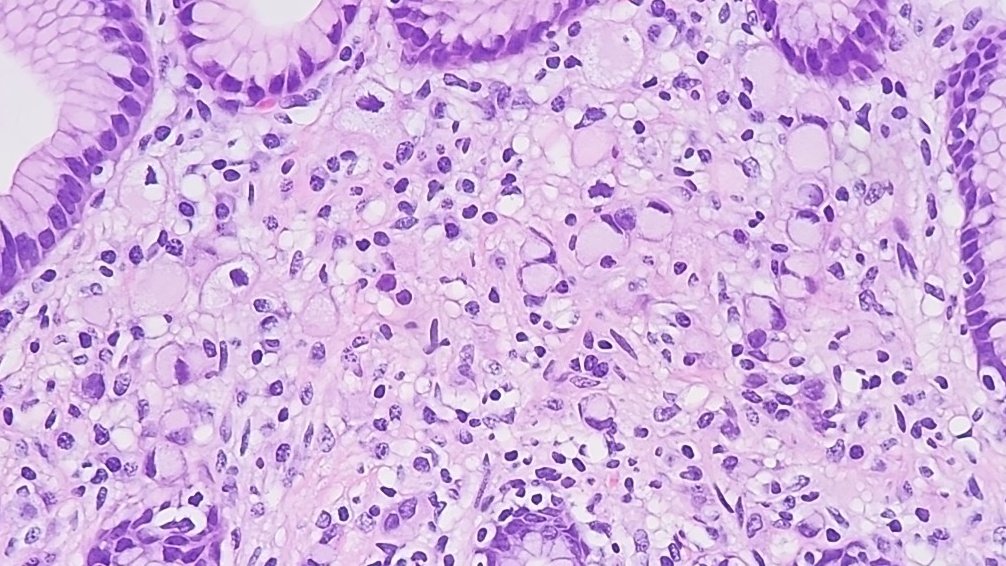

Herpes Esophagitis 3 Ms: Multinucleation Molding of nuclear contours Margination of chromatin #GIpath #pathology #PathTwitter #PathMatch24

Herpes Esophagitis

3 Ms:

Multinucleation

Molding of nuclear contours

Margination of chromatin

#GIpath #pathology #PathTwitter #PathMatch24